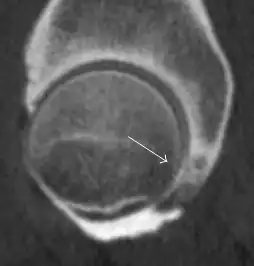

Synovial chondromatosis can be confidently diagnosed by X-ray when calcified cartilaginous chondromas are seen. However, other synovial proliferative processes, such as pigmented villonodular synovitis, require MRI for accurate diagnosis, although noncalcified synovitis can be suspected in radiographs by indirect signs, such as soft tissue swelling and/or erosions in the femoral head, femoral neck, or acetabulum (Figure 7).[1]

Figure 7:

-

Axial CT image of pigmented villonodular synovitis eroding the posterior cortex of the femoral neck.[1] -

Sagittal T2* gradient echo image showing a posterior soft tissue mass with hypointense areas secondary to hemosiderin deposition.[1] -

X-ray of synovial chondromatosis.[1] -

CT of synovial chondromatosis.[1]

In synovial proliferative disorders, MRI demonstrates synovial hypertrophy. In the case of PVNS, characteristic foci of low signal intensity related to hemosiderin deposition are better seen on gradient echo T2* images (Figure 7). In the case of synovial osteochondromatosis, the synovial hypertrophy is accompanied by intermediate signal cartilaginous loose bodies and/or low signal calcified loose bodies.[1]